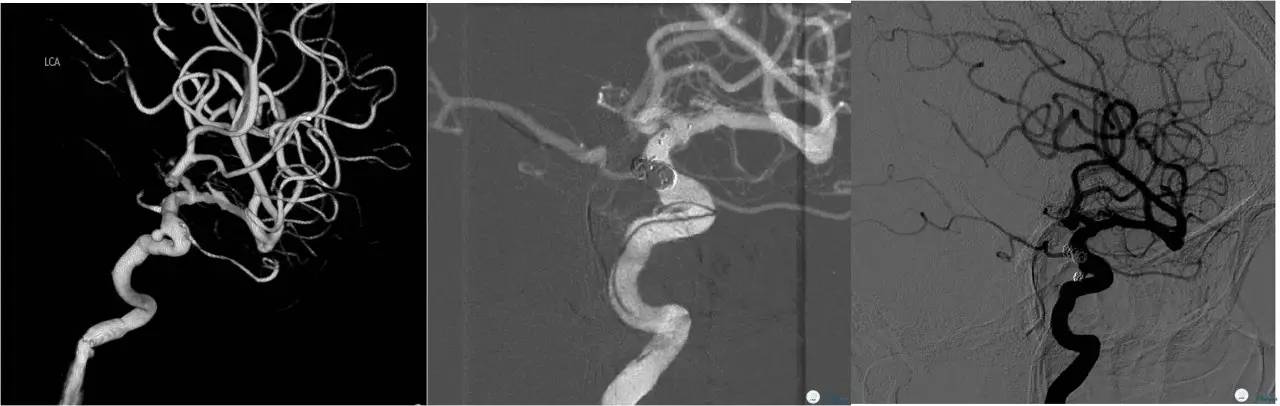

Case1 右ICA多发床突旁动脉瘤

术前VS术后即刻